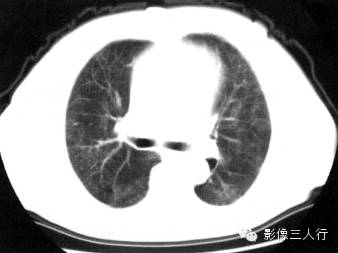

【报告范例1】

报告书写:胸廓对称,双肺小叶间隔增厚,边缘光滑,肺门及支气管血管束增粗、模糊,纵隔居中,其内未见肿大的淋巴结。心脏大小正常,胸壁软组织未见异常(图1)。

图1间质性肺水肿